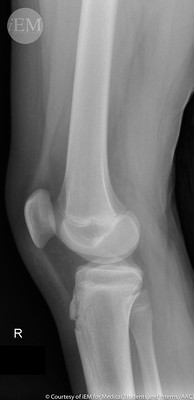

반월판 찢어짐

반월판은 무릎 관절을 완충시키는 연골 조각입니다. 찢어진 반월판은 무릎이 갑자기 비틀리거나 회전하는 결과로 발생할 수 있습니다. 이 부상은 운동선수에게 흔히 발생하며 통증, 부기 및 제한된 이동성을 유발할 수 있습니다.

관절염은 관절에 염증을 일으키는 만성 질환입니다. 골관절염, 류마티스 관절염 및 통풍을 포함하여 무릎 관절에 영향을 줄 수 있는 여러 유형의 관절염이 있습니다. 관절염은 무릎 관절에 통증, 부기 및 뻣뻣함을 유발할 수 있습니다.

수술 인대 또는 반월상연골 파열과 같은 보다 심각한 무릎 부상의 경우 수술이 필요할 수 있습니다. 진행된 관절염의 경우 무릎 교체 수술이 필요할 수 있습니다.